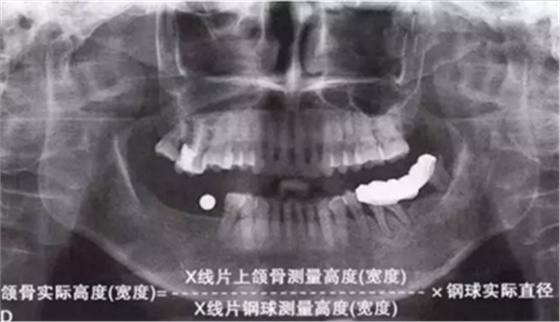

如何通過曲面斷層片測量出相對準確的數(shù)據(jù)?告訴大家一個很實用的方法,就是利用小剛球作為參照。

將小剛球放到口內(nèi)時拍攝曲面斷層片,拍攝后得到的結(jié)果就是這個樣子的:

因為小剛球的直徑是固定的,通過測量片子上小剛球的直徑,就能算出曲面斷層片的放大率,然后就能算出真實的骨高度了,這是一個很不錯的方法。